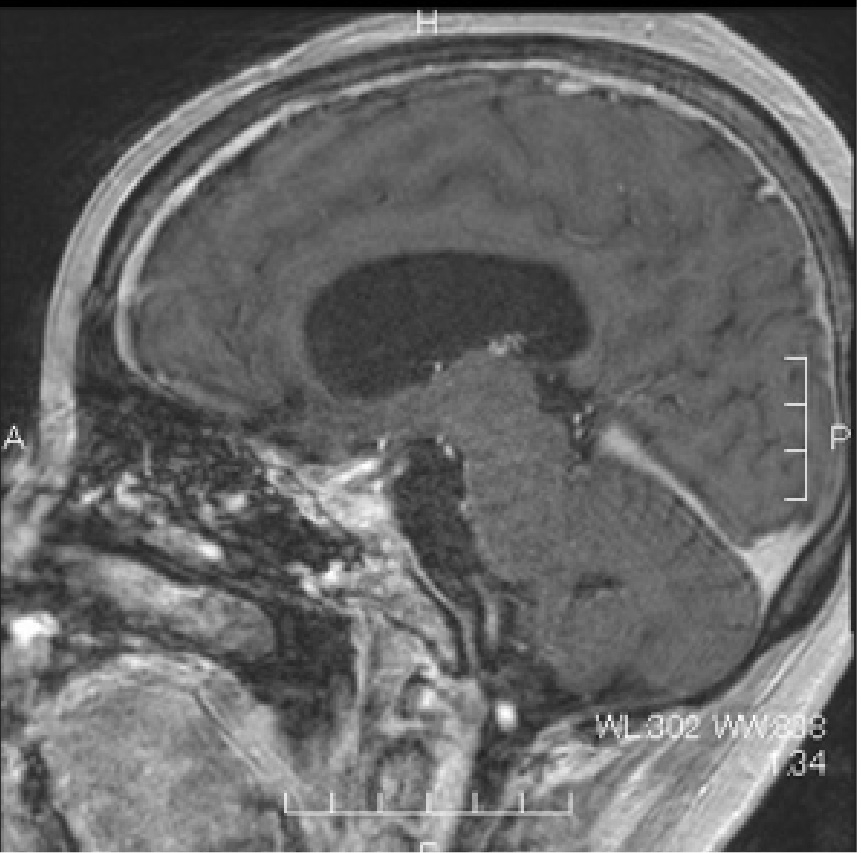

外視鏡と内視鏡を組み合わせて治療した腫瘍のMRI画像です。

髄膜腫:小脳、脳幹、聴神経などが圧迫されている

術後MRI